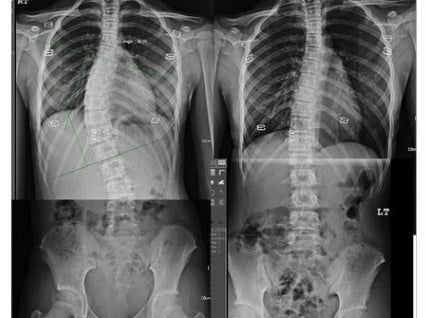

"Image from ISST Schroth Method." ISST Schroth, https://www.isstschrothmethod.com/isst-schroth/. Accessed 11 September 2025.

We will perform a detailed assessment of the child, adolescent or indeed adult in conjunction with analysis of any x-ray films available. Once the individual has been assessed and the scoliosis classified, an intensive and specific exercise programme will be developed.